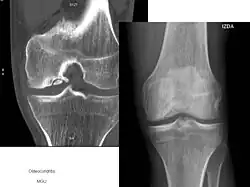

TOC generalmente causa dolor e hinchazón de la articulación afectada y bloqueos de la circulación. El examen físico revela un derrame, sensibilidad y crepitación. El TOC puede ser difícil de diagnosticar porque los síntomas parecen a otras enfermedades. Sin embargo, la enfermedad puede ser confirmado por los rayos X, la tomografía computarizada (CT) o imágenes de resonancia magnética (MRI) explora. OCD está clasificada por estas técnicas de imagen, o por artroscopia de la articulación, y representada en las fases (I, II, III y IV), de la progresión de la enfermedad. Tras el diagnóstico de la enfermedad puede ser tratado, dependiendo de su gravedad, por la reparación del cartílago.[5][6] El tratamiento no quirúrgico rara vez es una opción, ya que el cartílago tiene una limitada capacidad para curar. Como resultado, incluso moderados casos requieren algún tipo de cirugía. Cuando sea posible, no el tipo de gestión como protegidas peso (parcial o no del peso) y la inmovilización se utilizan. El tratamiento quirúrgico varía ampliamente e incluye la perforación de lesiones artroscópicas intactas, la seguridad de las lesiones del cartílago solapa con clavijas o tornillos, la perforación y la sustitución de cartílago enchufes, trasplante de células madre, y reemplazo de articulaciones.

TOC está clasificado por la progresión de la enfermedad en etapas. Existen dos clasificaciones de etapas más utilizados, uno es determinada por resonancia magnética de imágenes de diagnóstico, mientras que la otra está determinada por artroscopia. Sin embargo, ambas puestas en escena representan las condiciones patológicas asociadas con la progresión natural OCD.

Aunque la clasificación artroscópica de las lesiones osteocondrales se considera estándar, la puesta en escena Anderson RM es la principal forma de clasificación usado en este artículo.[7] Etapas I y II son lesiones estables. Etapas III y IV se describen las lesiones inestables en el que una lesión del cartílago ha permitido que el líquido sinovial entre el fragmento y el hueso.